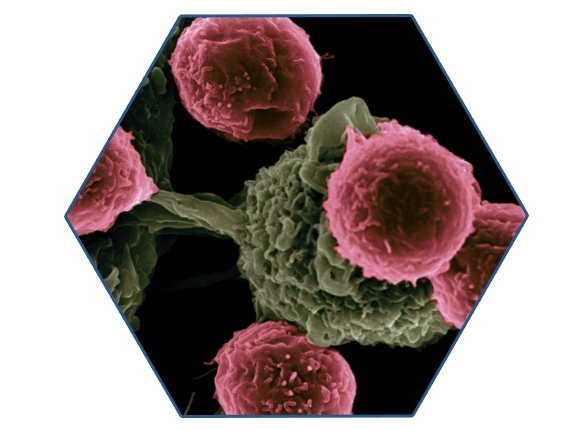

Journal of Advanced Oncogenomics